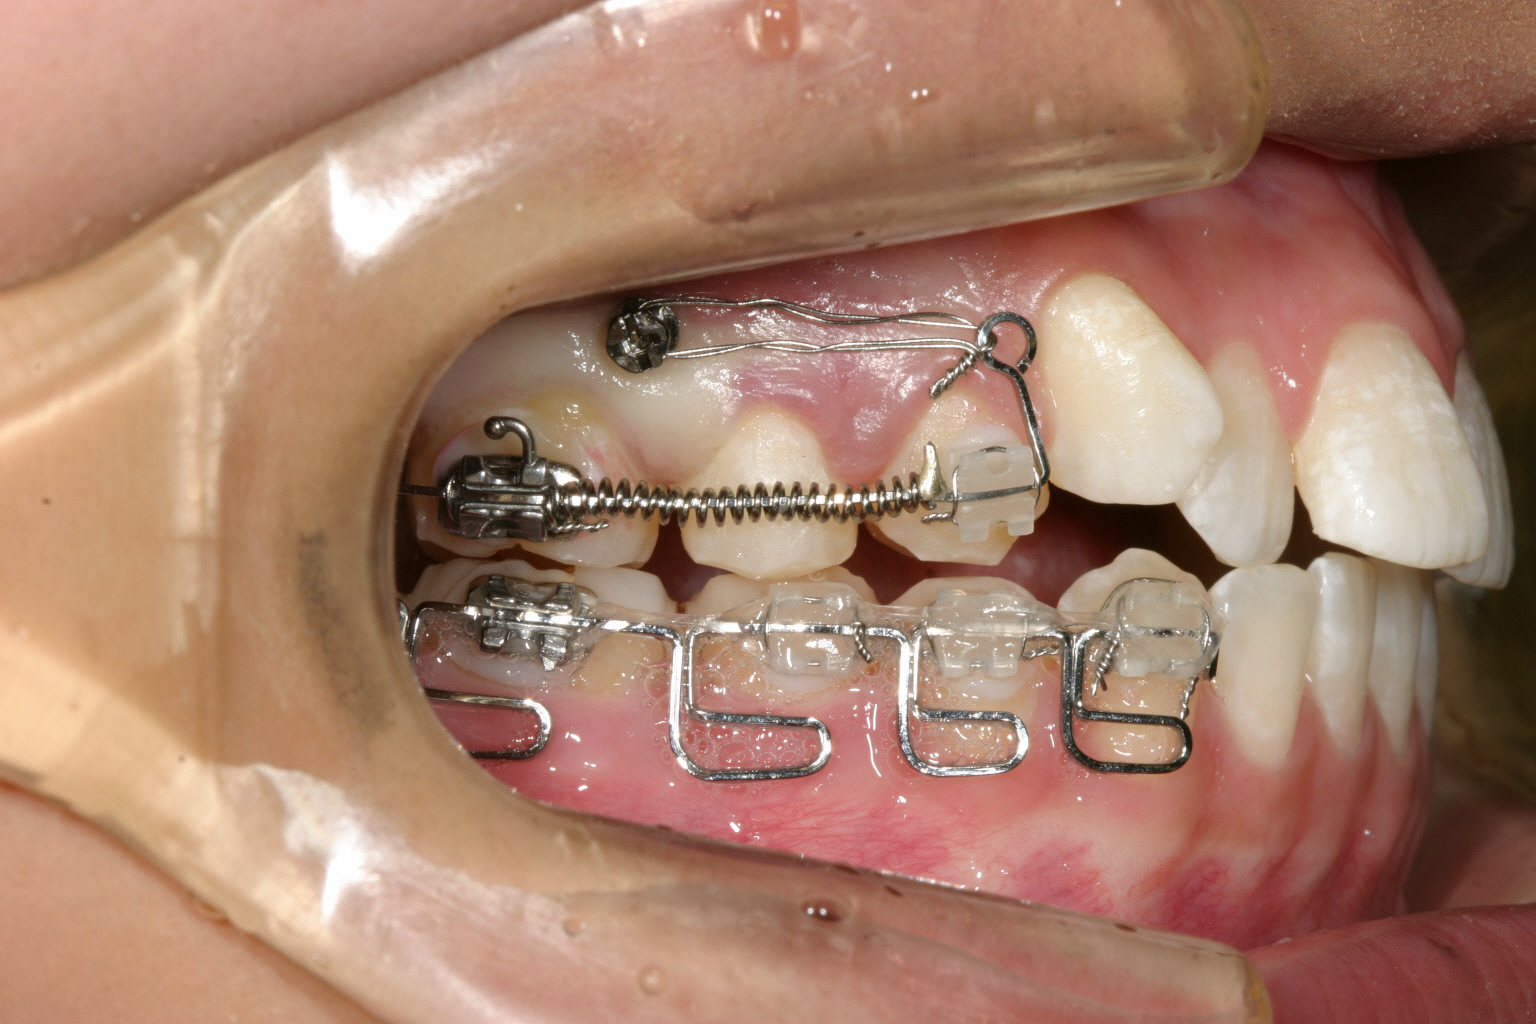

右の犬歯の突出が気になりますね~ 口の中を見ると単に糸切り歯が出てるだけなんだから入れればいいと簡単に考えるのですが 犬歯が並ばないのは奥歯が全体的に前に来ている為に犬歯の入るスペースが無く外に飛び出しているんです。 その為部分ワイヤーを用いて犬歯以後の臼歯を全体的に遠心移動(後ろに送る事)しました。

下顎は一見綺麗に見えるのですが右の奥から3本目を見てください。 歯が90°回転しているのが見受けられます。 こういった歯をインビザライン単独で治療するにはかなり難易度が高く治療に相当の期間がかかり 結果として上手く戻らない事が多いです。 その為今回は部分ワイヤーを併用しました。

インプラントとワイヤーとバネの力を利用して右側臼歯を遠心移動してるのが分ります。

マルチループワイヤーを用いて右奥から3番目の小臼歯が上手く回転し終わりました。

上にインプラントとワイヤーとバネです。 下はマルチループです。

回転途中の写真です。

写真上部にインプラントが見えます。